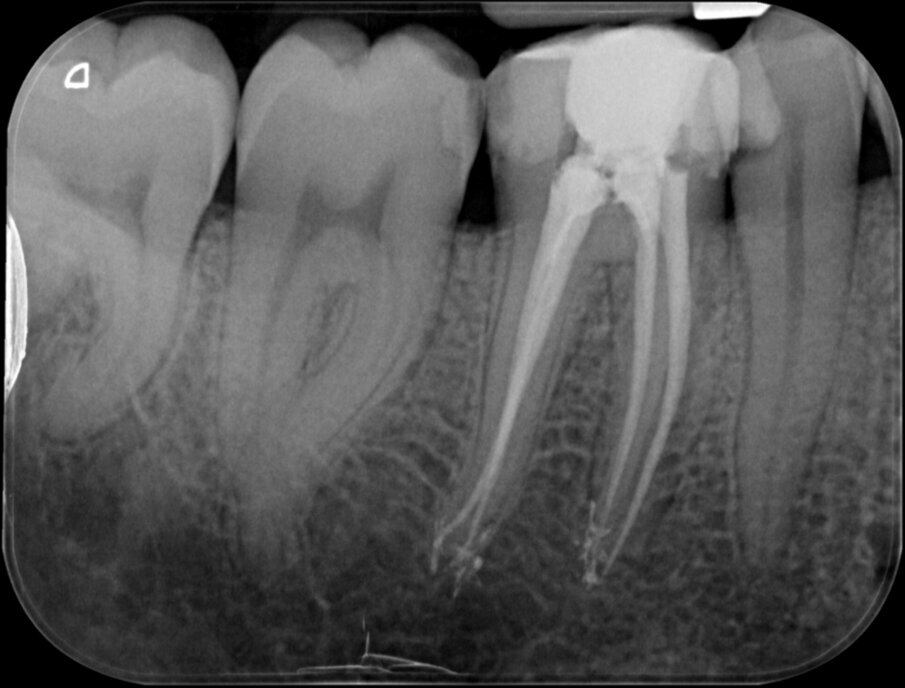

De eindfoto’s stemmen tot optimisme. Röntgenologisch lijkt voldaan aan al de eisen die Schilder aan de vorm van geprepareerde kanalen stelde.

1. Originele anatomie behouden

2. Continue taper

3. Foramen zo klein als praktisch

4. Positie van het foramen behouden

Er lijkt sprake van een gevuld systeem (afbeelding 3 en 4). De puffs in de laatste paar millimeter hebben geen klinische betekenis, maar zijn een normaal bijverschijnsel bij het obtureren van kanalen met een hydraulische obturatiemethode, gebruik makend van warme guttapercha. Hier kozen we voor Thermafil, wat een uitstekende reputatie heeft en de preferente vulmethode is van veel eminente clinici, zoals Buchanan en Ruddle. Vol vertrouwen presenteren we de resultaten aan de patiënt en we schrijven een brief aan de verwijzend tandarts dat het vervaardigen van een kroon nu kan geschieden zonder onaanvaardbare risico’s.